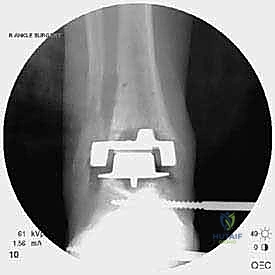

خطوات جراحة مراجعة مفصل الكاحل (Agility) بالتفصيل

تعتبر غرفة العمليات ساحة لإظهار البراعة الجراحية. عملية المراجعة تستغرق عادة من 3 إلى 5 ساعات وتتم عبر الخطوات المعقدة التالية:

الخطوة الخامسة: تركيب المفصل الجديد أو الدمج

يتم إدخال المفصل الجديد المخصص للمراجعة، والذي يحتوي غالباً على سيقان (Stems) تدخل عميقاً في عظمة الساق وعظمة الكاحل لضمان الثبات الميكانيكي. في حال وجود كسور في الكعب، يتم تثبيتها في هذه المرحلة.